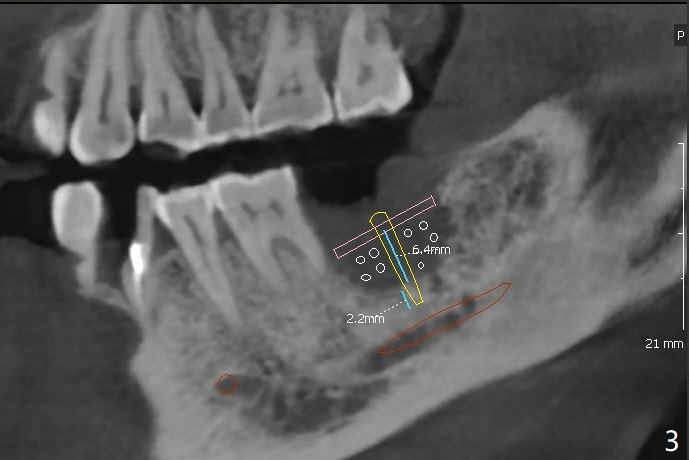

To increase bone density, use a large 8/9 mm trephine bur to harvest ramus block graft on the right with depth of 3 mm (Fig.4 red circle) after SRP in the lower arch and transfer to #18 socket (Fig.3 pink), fixed in place with a screw (probably 6 or 8 mm tenting one, yellow) after filling the socket with particulate bone graft (Vanilla, white circle).